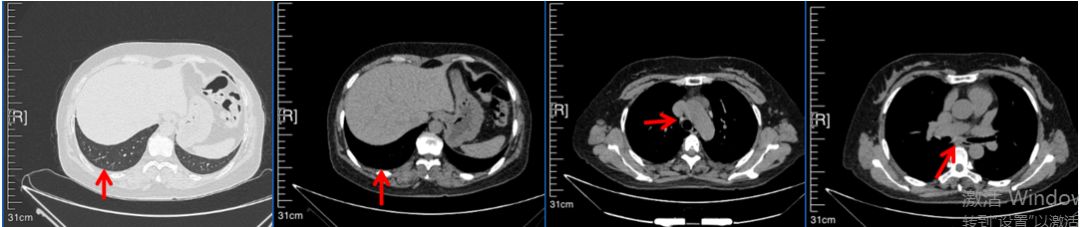

56岁,女性,无吸烟史饮酒史,既往体健。2023年02月患者体检发现肺占位性病变,胸部增强CT:右肺下叶后基底段结节;右侧锁骨上及纵隔内多发淋巴结肿大。PET-CT:右肺下叶周围型肺癌可能性大;1R、2L、3P、4R、4L及7组淋巴结转移可能性大。2023年02月就诊于本院胸外科行超声胃镜下纵隔肿物穿刺活检术,病理:结合免疫组化,符合肺腺癌。行NGS基因检测:EML4:exon20-ALK:exon20融合。PD-L1(克隆号22C3)TPS=55%。

临床诊断:右肺下叶恶性肿瘤cT1bN3M0,IIIB(第9版分期),纵隔淋巴结继发恶性肿瘤,锁骨上淋巴肿继发恶性肿瘤

治疗经过:2023年3月27日始行恩沙替尼靶向治疗至今,最佳疗效为PR,末次评效为维持PR。期间出现轻度肝功能异常(DILI 1级),对症处理后好转。截止目前PFS为26个月。

2023年2月20日基线检查

2024年6月复查PR(最佳疗效)

2024年12月复查维持PR

2025年3月复查维持PR